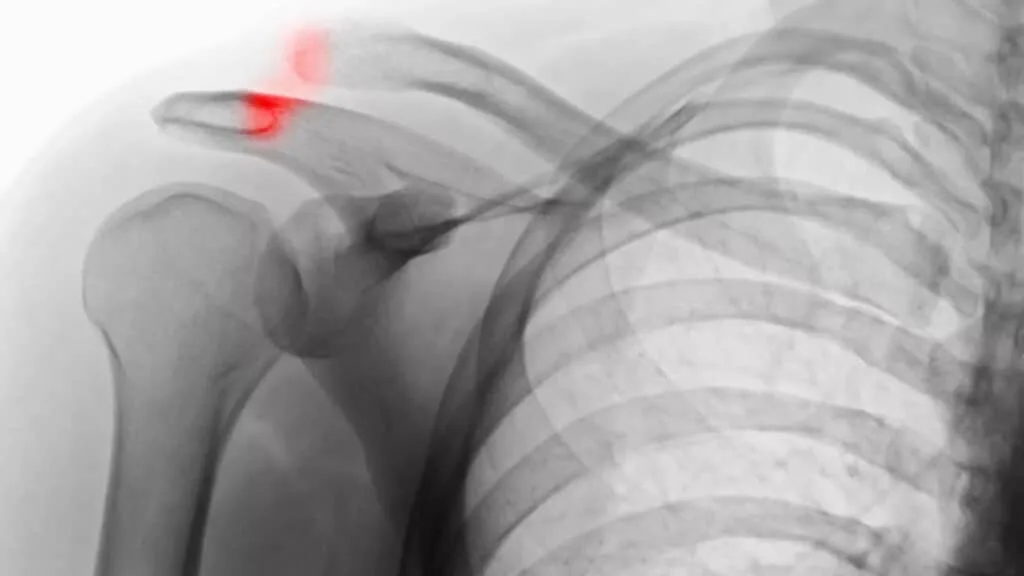

جداشدگی شانه آسیبی عجیب به نظر می رسد اما در حقیقت به کشش یا پارگی رباط ها در محل اتصال استخوان ترقوه با تیغه شانه (کتف) اشاره دارد.

این محل اتصال مفصل آکرومیوکلاویکولار نامیده می شود. هنگامی که این رباط ها بطور جزئی یا کامل پاره شوند ترقوه به جلو لغزیده و گاهی از کتف جدا می شود.

شدت و نوع بیماری با میزان و جهت جداشدگی مفصل و آسیب رباط که در اشعه ایکس نشان داده می شود تعیین خواهد شد.